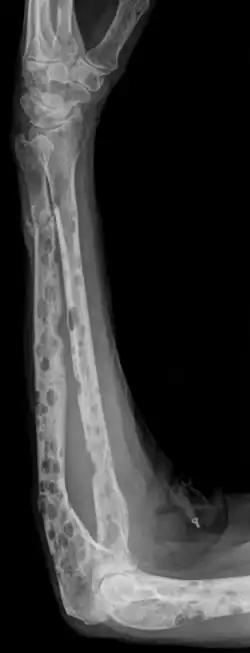

- Røntgenundersøgelser kan i nogle tilfælde påvise forandringer i knoglerne.

- CT-scanning bruges ofte i de tilfælde, hvor der er mistanke om knogleforandringer, der ikke kan påvises med røntgen.